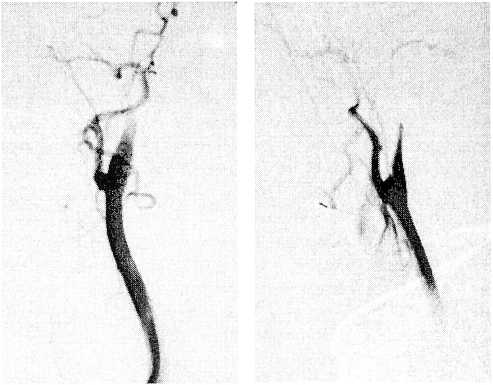

В послеоперационном периоде при выполнении эхокардиографии сердца обнаружено подвижное образование, выполняющее более 2/3 левого предсердия (внутрипредсердный тромб), размерами 2,52×2,93 см (миксома?) (рис. 10).

Рис. 10. Больная В., эхокардиография. Внутрипредсердный тромб левого предсердия 2,52x2,93 см